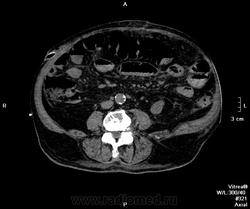

Пациент поступил ко мне через 6 дней после ушивания перфоративной язвы ДПК. УЗИ-сты увидели инфильтративно-жидкостные изменения в зоне оперативного вмешательства, пузырьки газа. Но смутило найденное образование в пространстве между правой долей печени и паранефрием. цель исследования - дифференцировать найденное между инфильтрацией и жидкостным скоплением.

-!!! в нативе желудок и петли кишечника не контрастированы - следы контраста в отдельных петлях тонкого к-ка (перед исследованиям он пил, по зонду ничего никуда - ни ни!!!), петли толстого и тонкого кишечника содержат умеренно повышенное количество воздуха и жидкого содержимого, с горизонтальными уровнями

- воспалительные изменения в проекции лапаротомного доступа, в пжк передней брюшной стенки, в абдоминальной жировой клетчатке и межпетельно

- диверткулище мочевого пузыря

- инфильтрат в левой седалищно-прямокишечной ямке

Инфильтрата в малом тазу (седалищно-прямокишечная ямка слева) тоже не увидела... немного жидкости стекло в таз после операции.